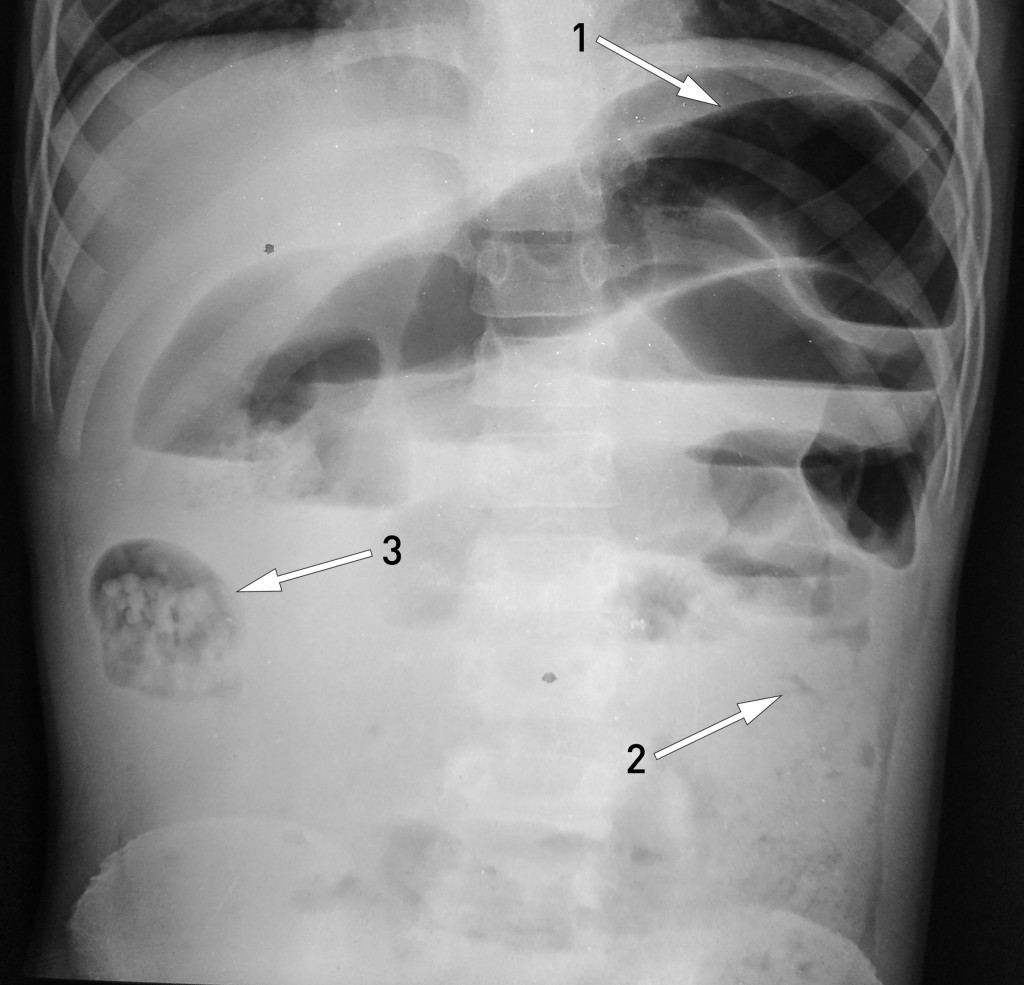

A ten-year-old boy was admitted as an emergency patient to a hospital in a poor region of Nepal. He had significant growth retardation, and had suffered from stomach pain, vomiting and a distended abdomen for the previous three days. He had not produced any stool but had excreted two live roundworms per rectum. Erect abdominal x-ray (x-ray image) showed distended intestinal loops (arrow 1), but a normal colon (arrow 2), hence findings that were consistent with mechanical intestinal obstruction. We suspected that an accumulation of roundworms in a segment of the intestine in the right flank (arrow 3) – most likely in the small intestine or right hemi-colon – had caused an ileus.